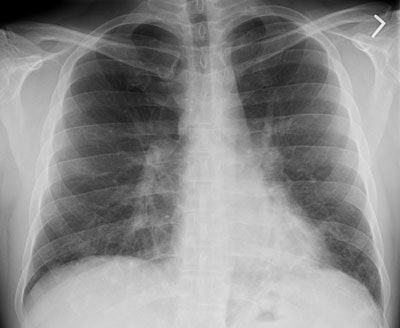

The patient below presented with complaints of cough, malaise, and a low-grade fever. The chest radiograph revealed some patchy left lower lobe airspace disease and vague nodular shadows- particularly in the lower lung zones. A chest CT was performed and demonstrated multiple nodular airspace abnormalities with variable margins. The lesions did not improve despite antibiotic therapy and all cultures were negative. Click images to enlarge. |